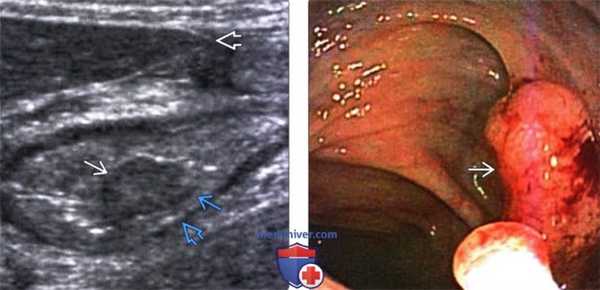

(Левый) Опухоль печеночного изгиба. Определяется циркулярное гипоэхогенное утолщение и утрата нормального слоистого строения стенки кишки. Определяется экстрамуральный нодулярный отросток опухоли, тянущийся в медиальную сторону в околоободочную клетчатку, а также другой отросток, прорастающий брюшину с латеральной стороны, что определяет стадию Т4.

(Правый) Этот же пациент. При КТ с контрастным усилением определяется опухоль печеночного изгиба в виде циркулярного утолщения стенки ободочной кишки, сопровождающегося поражением и утолщением париетальной брюшины с правой стороны, что соответствует стадии Т4.

(Левый) При УЗИ у пациента с полипоидальной карциномой в просвете поперечной кишки определяется гипоэхогенное новообразование. Эхогенная подслизистая и гипоэхо генная мышечная оболочки интактны, что определяет стадию Т1. Обратите внимание на нижний край печени.

(Правый) У этого же пациента при колоноскопии в просвете видно полипоидное новообразование, представляющее собой полипоидную карциному.